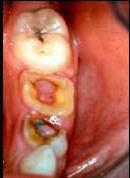

- 单项选择题临床上牙髓息肉一般见于 ( )

E、慢性增生性牙髓炎